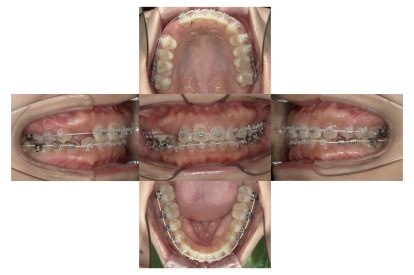

上下顎叢生(上下の前歯のガタガタ)のケースです。

装置はラビアル(上下表側)で、上下顎の小臼歯を4本抜歯を行っています。抜歯したスペースを使って、上下の前歯の後方移動と叢生(ガタガタ)の改善を行っています。

主訴 歯並びが悪く、舌を噛んでしまうのを治したい。

年齢・性別 27歳 男性

お住まいの地域 東京都大田区

治療方針 抜歯スペースを利用して上下前歯の叢生(ガタガタ)の改善

抜歯部位 上下顎左右第一小臼歯

使用装置 ラビアル(上下表側)、顎間ゴム

治療期間 3年1か月

治療回数 30回

治療経過